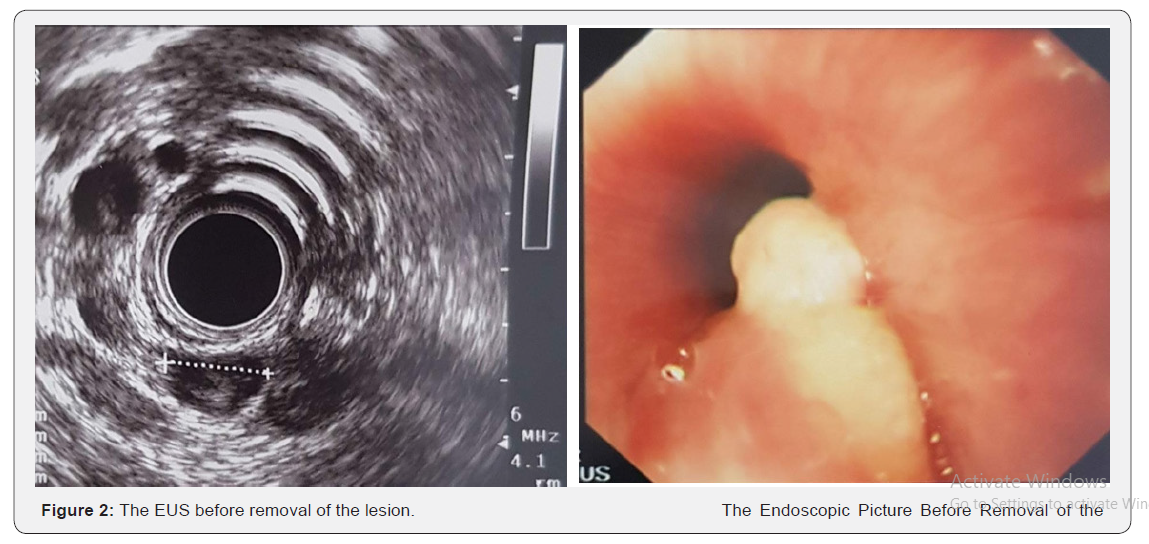

A 22-year-old nonsmoker female with negative past medical and surgical history presented for dysphagia of few monthsduration. She had dysphagia mainly to solids with globus sensation and frequent throat clearing without odynophagia, regurgitation, reflux, dyspepsia or weight loss. No previous medications were taken. Family history was noncontributory. Her Physical exam was non-significant. Her CBCD did not show anemia or any other abnormalities. Esophagogastroscopy was performed showing 1cm yellowish submucosal lesion 16cm from the incisors just below the upper esophageal sphincter. Patient was referred for endoscopic ultrasound (EUS) that showed sessile polypoid lesion with overlying yellowish granular mucosa. Endosonographically, the lesion measured 10mm*7mm, was hypoechoic with a central calcification and appeared to arise from the mucosa and superficial submucosa corresponding to a granular cell tumor of the upper esophagus. No para-esophageal adenopathy noted. EMR was successfully done using methylene blue injection for a good elevation followed by snare mucosa resection with no complications. Pathology showed infiltrative tumoral proliferation composed of nests or trabeculae made up of large, round and oval cell having brightly eosinophilic granular cytoplasm. The cell borders are indistinct, and the nuclei are uniformly round and centrally situated. Pathology characteristics confirmed granular cell tumor (Figure 1).

TGCTs are rare tumors of GI tracts. Commonly they are found in the skin and subcutaneous tissues (70% of cases). 8% only of GCTs are found in GI tract, most of them are at the esophagus.1% only of esophageal tumors are GCTs [1-5]. Abriksoosoff firstly described GCTs in 1926 [1]. Those tumors arise from Schwann cell which was proven based on immunohistochemical and ultrastructural findings [6]. Esophageal GCTs are more common in females, and in the age group between 40-60 years [5]. Their presence at younger age such as in our case in less commonly reported. Beside the uncommon age presentation, the location of the tumor contributes also to the uniqueness of the case. Most GCTs are found in the middle to distal esophagus. Goldblum et al. [7] reported that 92% of esophageal GCTs were located in the distal esophagus. Also, Wand & Liu [8] found that 80% of cases are in the middle and distal esophagus. While small lesions are incidentally found during endoscopy, larger lesions >1cm presented with dysphagia and chest pain. It can mimic also typical symptoms of GERD. Endoscopically, GCTs appears as isolated, sessile, submucosal lesions that are yellow-white in color, firm, with a negative pillow sign [9]. They commonly arise from submucosa but can involve the mucosa or muscularis propria. EUS is essential in diagnosis by locating the origin of tumor precisely the layer from which it is arising and through fine needle aspiration (FNA). In addition, EUS can also contribute to the planning of the resection. They usually appear as hypoechoic and homogeneous lesions, with clear borders. Palazzo et al reported endoscopic features of 21 GCTs with the following characteristics: (1) tumor size < 2 cm in 95% of cases; (2) a hypoechoic solid pattern in all cases; and [3] a tumor arising in the inner layers in 95% of cases [10] (Figure 2).